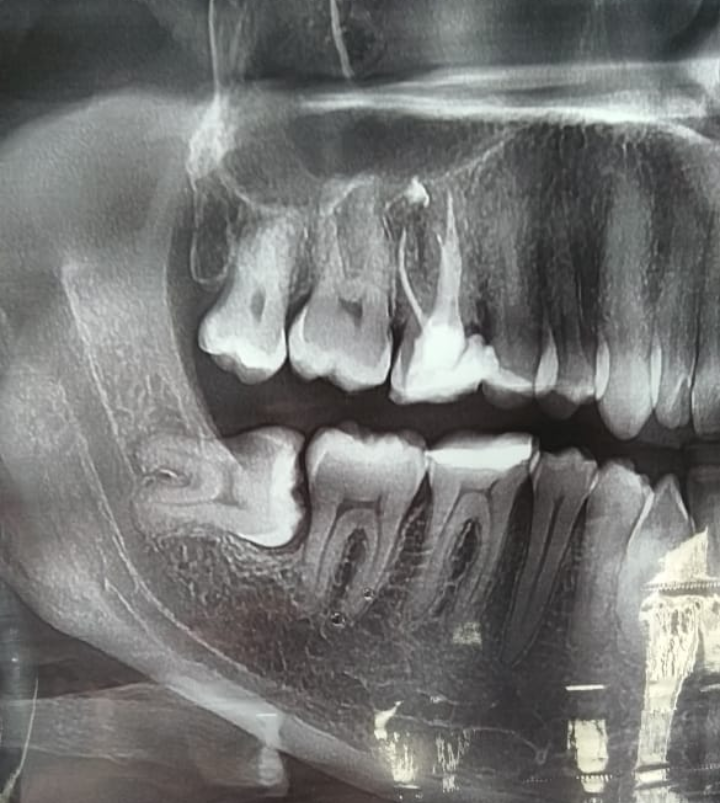

Правильный диагноз можно поставить только с помощью 3D-сканирования области с зубом мудрости. На рентгенографии врач сможет увидеть точное место локализации воспаления. Кроме этого, итог рентгенологического исследования помогает правильно подобрать методику лечения или принять решение о необходимости хирургического вмешательства.